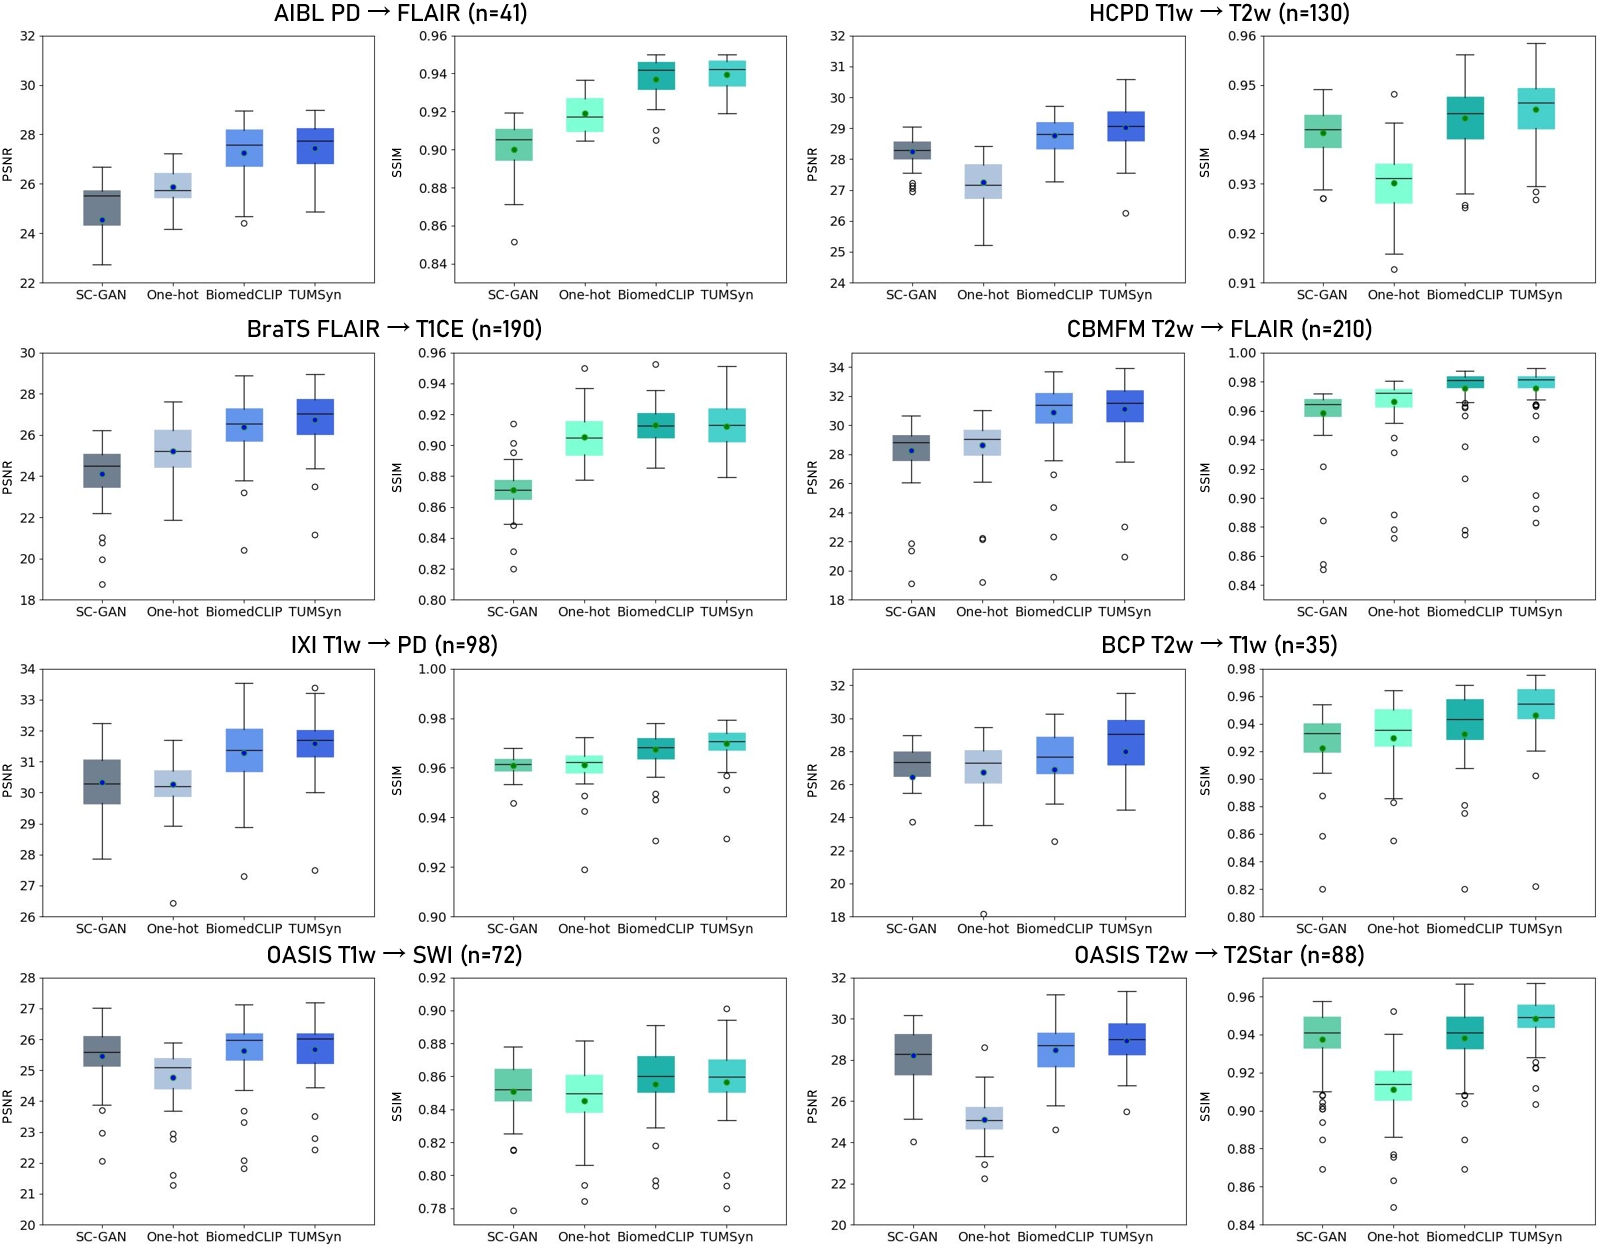

TUMSyn in improving synthesis accuracy and versatility

To study TUMSyn’s synthesis accuracy and ability for diverse tasks using a unified model, we performed a systematic evaluation of TUMSyn on a broad spectrum of synthesis tasks using nine internal datasets. First, we compared TUMSyn with three competing models, including SC-GAN [27], One-hot model, and BiomedCLIP [20] model. SC-GAN is a self-attention-based conditional GAN for MR neuroimaging synthesis, and it is a task-specific network trained for independent tasks. The One-hot model and BiomedCLIP model, sharing the identical image synthesis model architecture as ours but utilizing one-hot encoding and BiomedCLIP for text embedding, respectively, are employed to evaluate the effectiveness of our pre-trained text encoder on brain MRI synthesis. The comparison includes eight synthesis tasks for commonly used MRI modalities on internal test sets (Fig.3). The results exhibit that TUMSyn achieves the highest performance for all the tasks. Specifically, TUMSyn significantly outperforms task-specific SC-GAN with both improved PSNR (up to 2.86 dB) and SSIM (up to 0.044). This finding suggests that training on varied data and tasks enables the model to learn generic feature representations, thereby enhancing its overall synthesis ability for different scenarios. Besides, compared to the One-hot model, leveraging text prompts can lead to greatly improved synthesis performance, probably because text prompts can precisely instruct imaging parameters of target images.Moreover, it is shown that, although BiomedCLIP is trained on substantially larger biomedical datasets, our pre-trained text encoder empowers the synthesis model to achieve higher PSNR (up to 1.12 dB) and SSIM (up to 0.010) across eight tasks. This suggests that allowing the text encoder to learn task-related information, namely MR imaging parameters, is critical in enhancing MR image synthesis performance, especially for the downstream tasks that requiring precise prompt features as guidance.